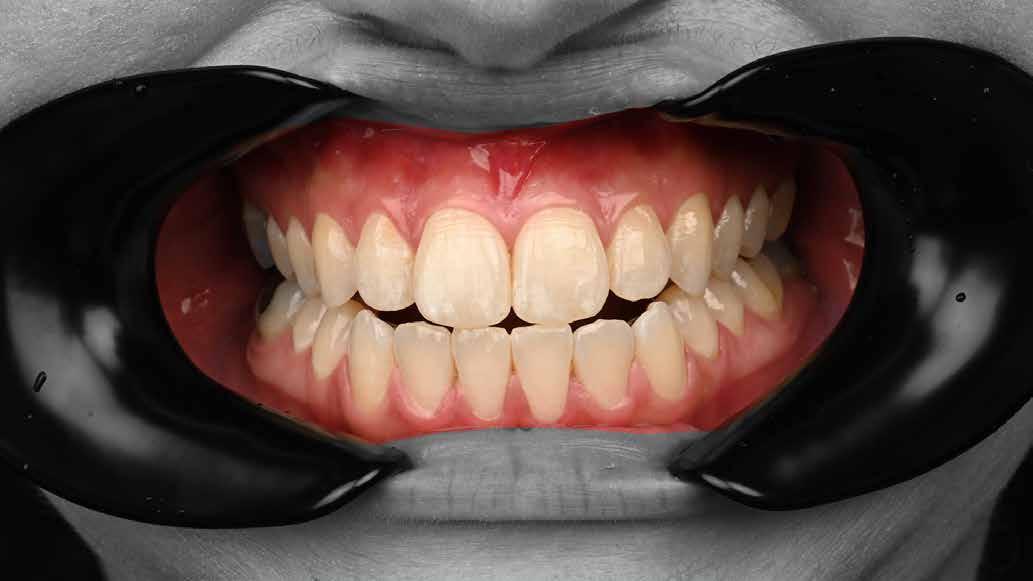

Interdiszciplináris fogászati kezelés myofunkcionális készülék, alignerek és protetikai ellátás alkalmazásával

MED. DENT Abradált frontfogakkal rendelkező felnőtt páciens interdiszciplináris kezelése